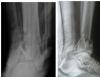

ORIF of Pilon fracture

Comminuted Pilon fracture (closed)